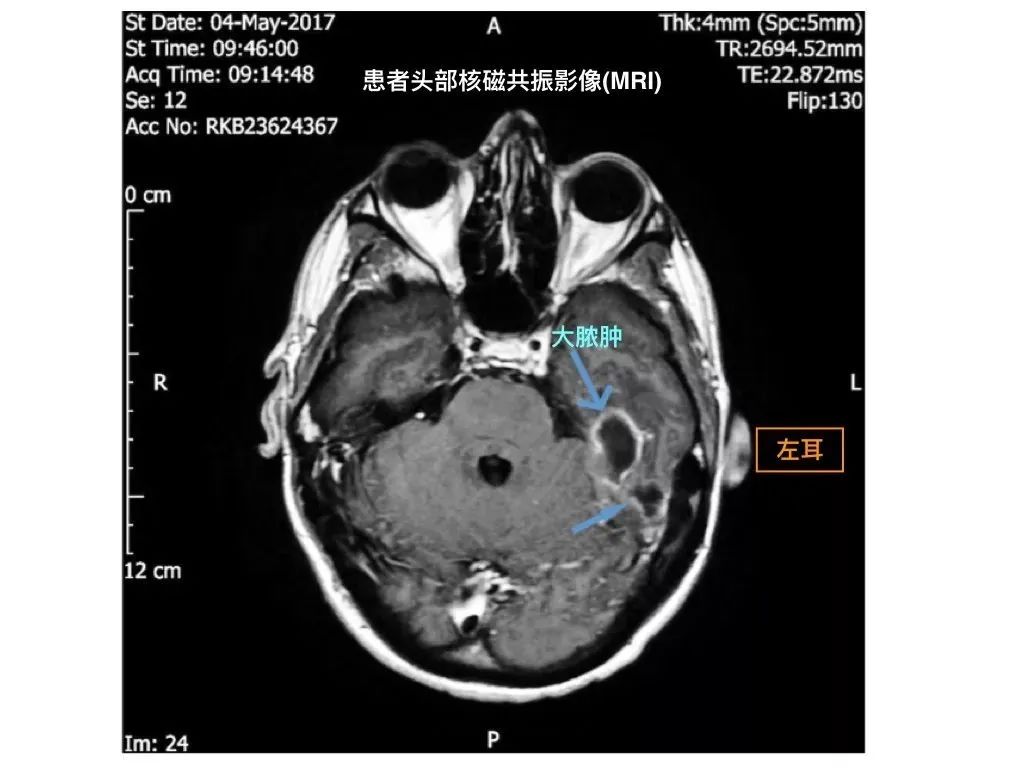

医生们给他做了一个头部的核磁共振,发现天呐,小伙儿脑子里有脓肿,大的脓肿有2.9x1.7x0.9cm^3,大概一枚葡萄那么大,外耳道里还充满着软组织密度影,原来是坏死性外耳道炎侵犯了颅脑。他的癫痫发作和暂时记忆丧失,可能是因为脓肿压迫了大脑。

患者的MRI图丨来源:论文1